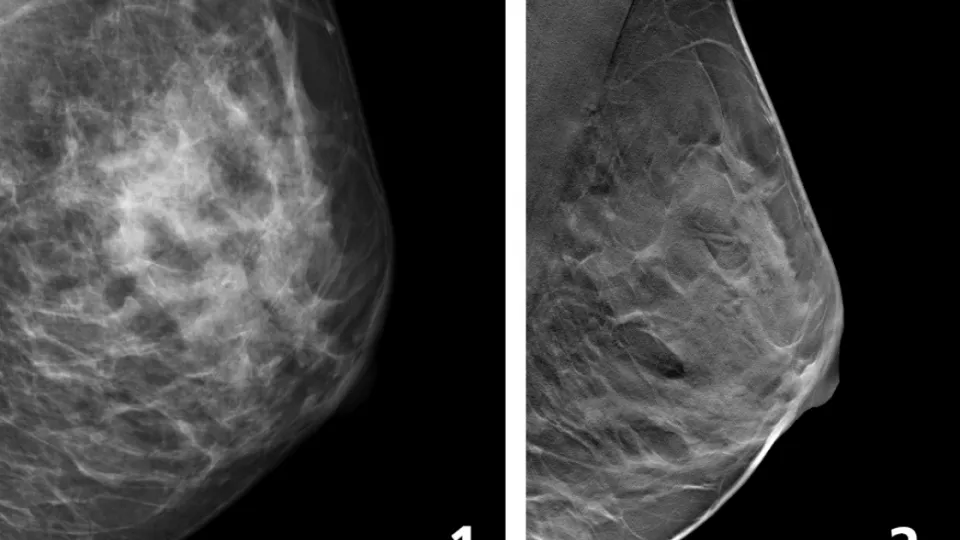

Fewer Breast Cancer Cases Between Screening Rounds With 3D-Mammography

3D-mammography reduces the number of breast cancer cases diagnosed in the period between routine screenings, when compared with traditional mammography, according to a large study from Lund University in Sweden.

A large prospective screening study conducted at Skåne University Hospital in Malmö (Malmö Breast Tomosynthesis Screening Trial) between 2010 and 2015 included almost 15,000 women who received both 3D-mammography and traditional mammography. In 2018, the researchers published results from the trial showing that 3D-mammography detects just over 30 percent more cases of breast cancer compared to traditional mammography.